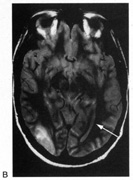

Fig. 5. Macula-splitting hemianopia. A 47-year-old man with AIDS and sudden onset of poor vision. A. Fields show complete left hemianopia. B. MRI shows lesion of right lateral occipital cortex, affecting distal optic radiations. Biopsy showed nonspecific encephalitis.

Fig. 6. Lesion of temporal optic radiation. Left superior quadrantanopia, respecting horizontal meridian (A), from infarct of right medial temporal lobe, in posterior cerebral artery territory (B). (From Rosen ES, Eustace P, Thompson HS, Cumming WJK [eds]: Neuro-Ophthalmology. London: Mosby, 1998.)